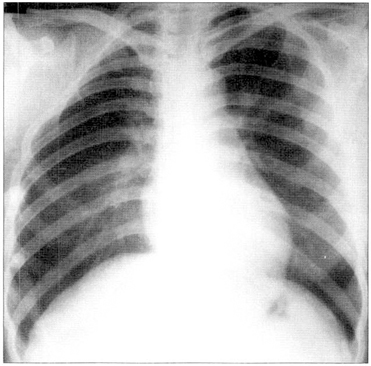

img <폴란드증후군 환자의 흉부엑스레이>

• 01 환자의 대부분은 가족력이 없어 이유를 모르지만 매우 드물게

부모와 자식에게 같은 증상이 나타나고 질환을 갖지 않은 부모에게

태어난 형제들이 동시에 이 질환을 갖는 등 가족적인 패턴이 보고됨

• 02 특정 동맥의 발달 장애 또는 다른 물리적인 요인들에 의해 발생하며,

그 결과 초기 태아기 때 혈류 흐름에 장애가 생기거나

혈류 공급이 줄어들어 손상을 받는다는 가설을 발표함